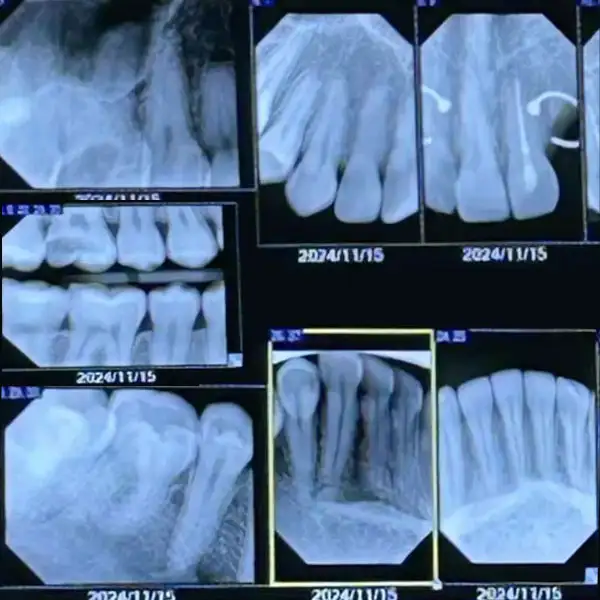

A comprehensive oral examination to assess teeth, gums, bite, and overall oral health. Using advanced digital X-rays, hidden problems such as cavities, infections, bone loss, and impacted teeth can be detected at a very early stage — even before symptoms appear.

Early diagnosis allows for timely and minimally invasive treatment, helping prevent pain, complications, and costly dental procedures in the future. Regular dental checkups play a vital role in maintaining a healthy smile and overall well-being.